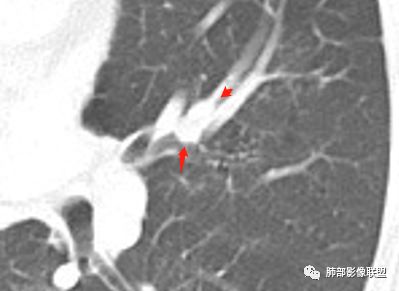

我们捋一捋

几个结节

下面这一支堵了

前后对比,这些结节其实是没引起支气管远端病变的

南大标注,这几个确实结节没有阻塞支气管,感觉是在血管分叉地方。

@南边 关键是上面这几个结节有的密度度,有的密度低。与下面堵塞支气管的结节样改变是否不是一回事,

后头看前片似乎当时腔内壁稍增厚一点